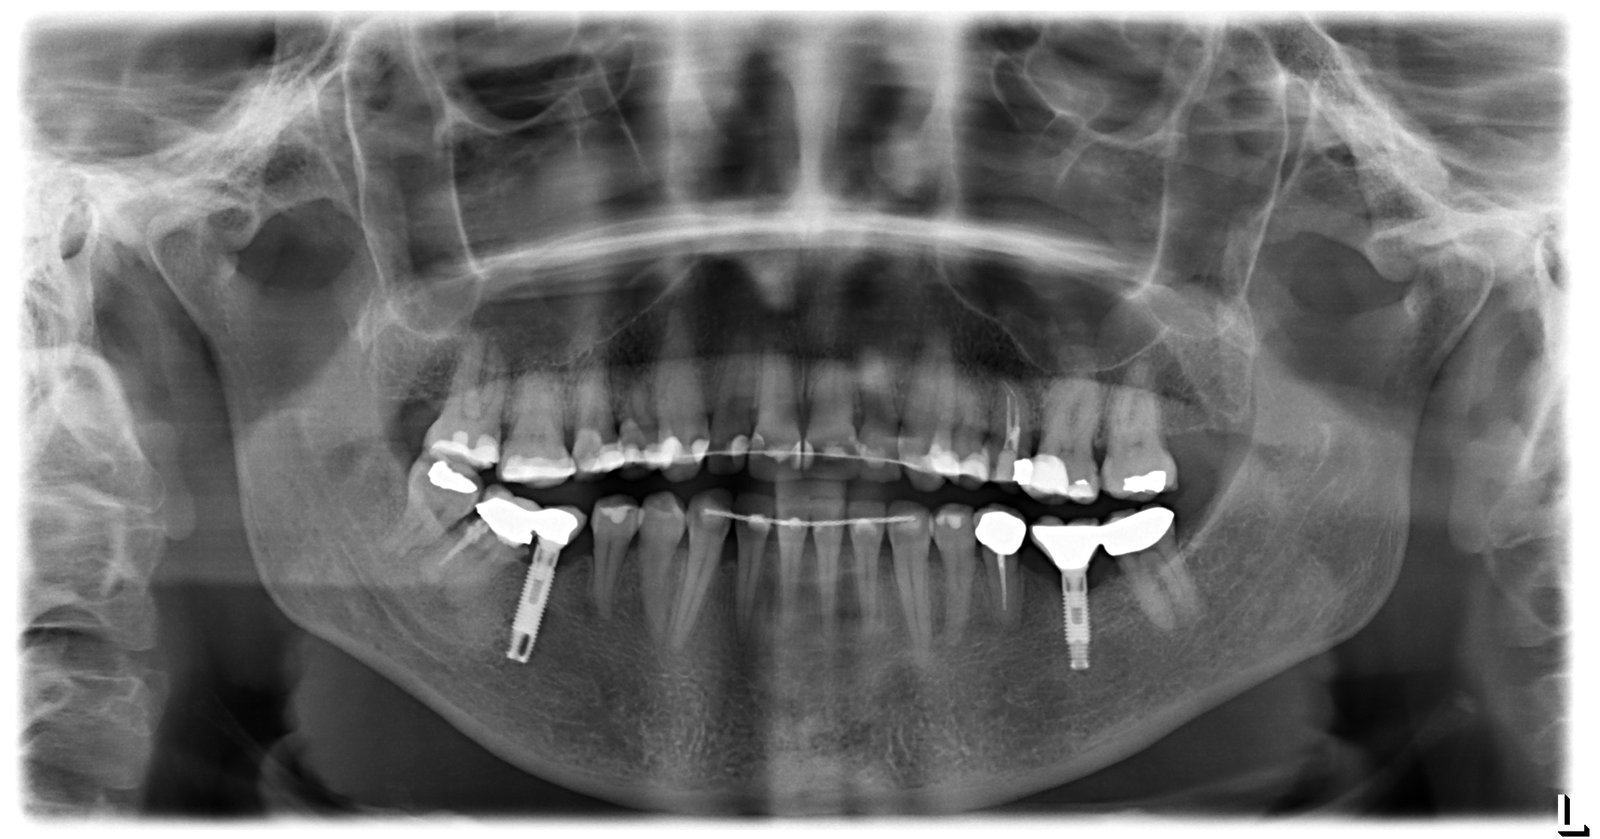

esta paciente se puso los implantes hace aproximandamente 20 años, en la clinica donde se los pusieron le dicen q no tienen su ficha y q pueden ser de 3i, [...]

El paciente acude con fractura de los implantes 1.2 y 2.2. Necesitaríamos saber marca implante y conexión de los implantes 1.1 y 2.1. Saludos y gracias.

Hola , no sabemos que implante son el de 24 y 25 , si me podeis ayudar gracias.